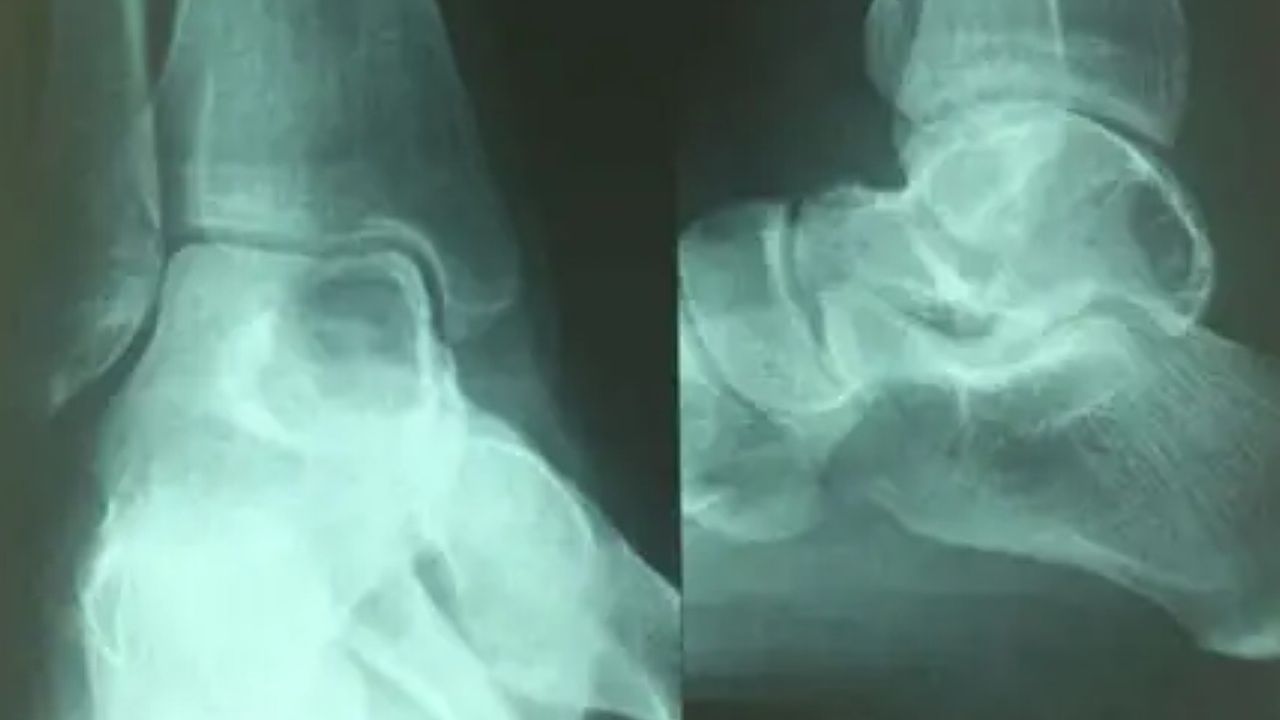

Anevrizmal kemik kisti, kemik içerisinde oluşan, kanla dolu, iyi huylu bir tümördür. "Anevrizmal" terimi, kistin içindeki genişlemiş kan damarlarına işaret eder. Bu kistler, genellikle gençlerde ve çocuklarda görülür ve en sık uzun kemiklerde, özellikle de omurga ve bacak kemiklerinde yerleşirler. Kistler genellikle ağrısızdır, ancak büyüdüklerinde kırığa neden olabilir veya çevredeki kemikleri etkileyebilir. Teşhis, genellikle X-ışınları, BT taramaları ve MR taramaları kullanılarak yapılır. Görüntüleme yöntemleri, kistin büyüklüğünü, şeklini ve çevredeki kemik dokusu ile ilişkisini gösterir.